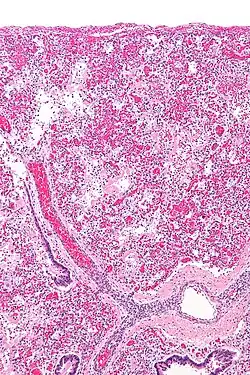

Leukocyte-mediated pulmonary inflammation is a key pathophysiological mechanism involved in ARDS.[2] This is presumed to cause Diffuse Alveolar Damage (DAD) [Fig 2]. On histologic examination, DAD is present in 40-60% of patients clinically diagnosed as having ARDS.[3]